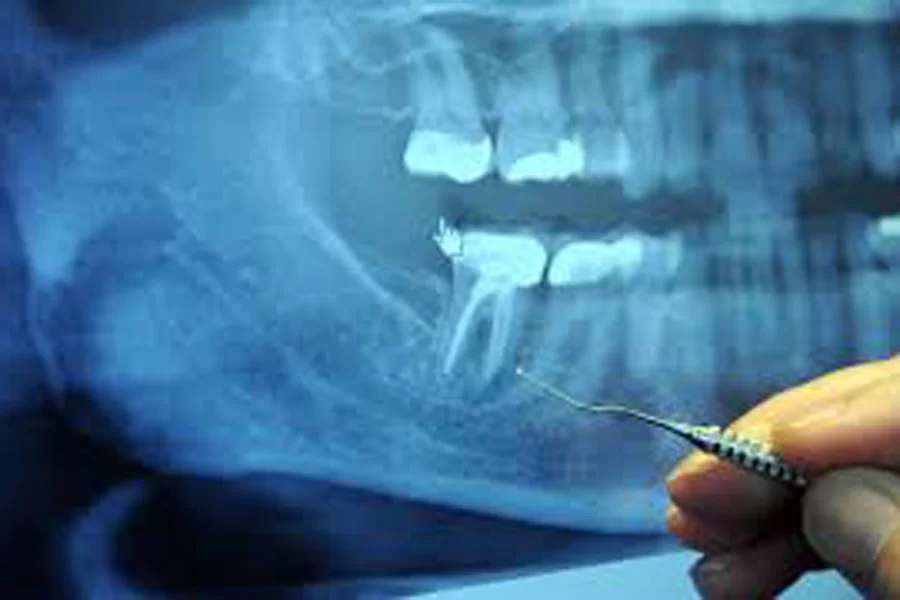

胎児を守る「低用量デジタルレントゲン」と「防護エプロン」

妊娠中のレントゲン撮影に抵抗を感じる方は非常に多いですが、歯科用レントゲンは放射線量が極めて微量です。

被ばく量の比較

私たちが1年間に自然界から浴びる放射線量(約2.1mSv)に比べ、歯科用レントゲン1枚の線量はその約100分の1以下です。

物理的な遮断

撮影部位はお口であり、お腹からは物理的に距離があります。

さらに、X線を遮断する鉛入りの「防護エプロン」を必ず着用していただくことで、お腹の赤ちゃんへの被ばくはほぼゼロに抑えられます。

最小限の撮影

原則として緊急性が低い場合は撮影を控え、どうしても診断に必要な場合のみ、最小限の枚数で撮影します。